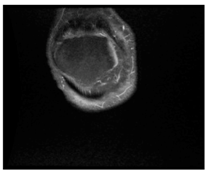

In this section, we present and analyze the results obtained with the proposed method, and compare it to methods proposed in similar works. The proposed watermarking system is implemented using MATLAB and executed on a Windows machine with the following characteristics: Intel R Core i5 processor, 4 GHz, 4 GB RAM, and Microsoft Windows 8 Professional operating system platform. In our experiments, we have used DICOM images of size 512 × 512 pixels as shown in Table 1.

Table 1.

Original images.